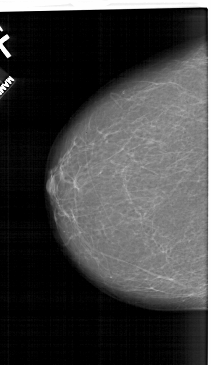

A_1150_1.LEFT_MLO

LEFT_MLO LINES 6226 PIXELS_PER_LINE 3721 BITS_PER_PIXEL 12 RESOLUTION 43.5 NON_OVERLAY